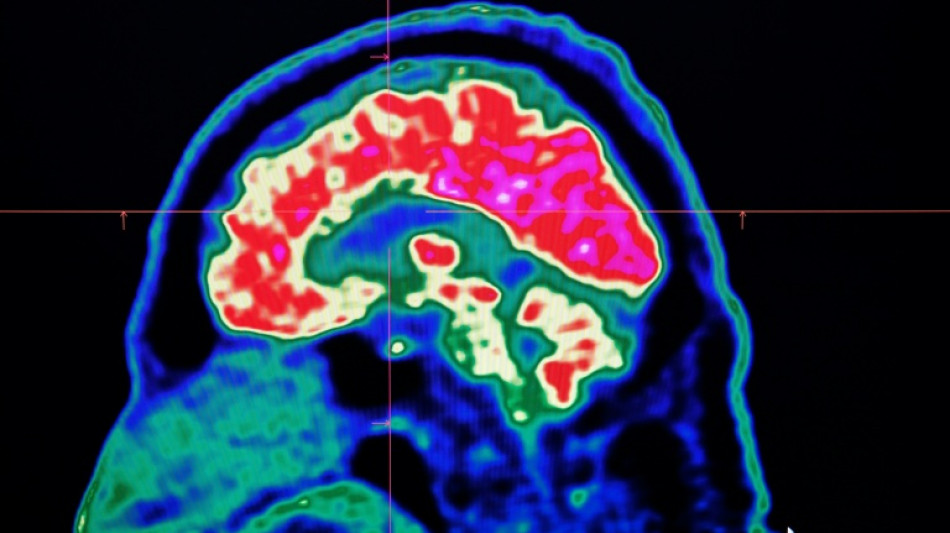

Final report casts doubt on existence of Canada mystery brain illness

Final report casts doubt on existence of Canada mystery brain illness / Photo: Fred TANNEAU - AFP

A Canadian medical report published Friday found no evidence linking environmental factors to an unusual set of neurological symptoms affecting hundreds of people, a five-year saga that has shaken a small Atlantic province.

In 2021, health officials in New Brunswick launched an investigation involving 48 patients with a range of neurological symptoms but no apparent common illness. These included muscle spasms, memory loss, hallucinations and balance issues.

Some in the province of less than a million people began describing the condition as a mystery brain disease.

Provincial officials said at the time that the patient group could be suffering from a new disease not previously seen in Canada and began using the term "possible neurological syndrome of unknown cause."

But the provincial investigations that followed, including the final report released Friday, dismissed claims that there was anything linking the patients other than a reported set of symptoms -- and a single neurologist, named Alier Marrero.

The first investigation, which concluded in 2022, "found no evidence of a common illness among these patients."

But in 2023, Marrero reported additional people complaining of neurological symptoms and the patients' stories continued receiving widespread media coverage.

Marrero said that while the condition could not be diagnosed, he believed the patients had elevated levels of certain substances -- like herbicides or toxic metals -- in their systems, suggesting an environmental cause for the illness.

New Brunswick launched a new investigation, this time looking at data from 222 patients, about 75 percent of whom lived in or around the city of Moncton.

A Journal of the American Medical Association study published last year found no evidence of a common mystery disease, either.

"We are able to conclude that our investigation found no evidence of a widespread issue among this patient group," the report said.

"We do not feel that exposure to these substances is a contributing factor to most patients' illness," it added.

"Patients were reported to (the province) as having an undiagnosed illness; however, our findings suggest that it is possible that many patients do have illnesses that can be diagnosed," it said.

The report also recommended that before a neurological condition is declared "undiagnosed," a patient must be seen by two specialists.